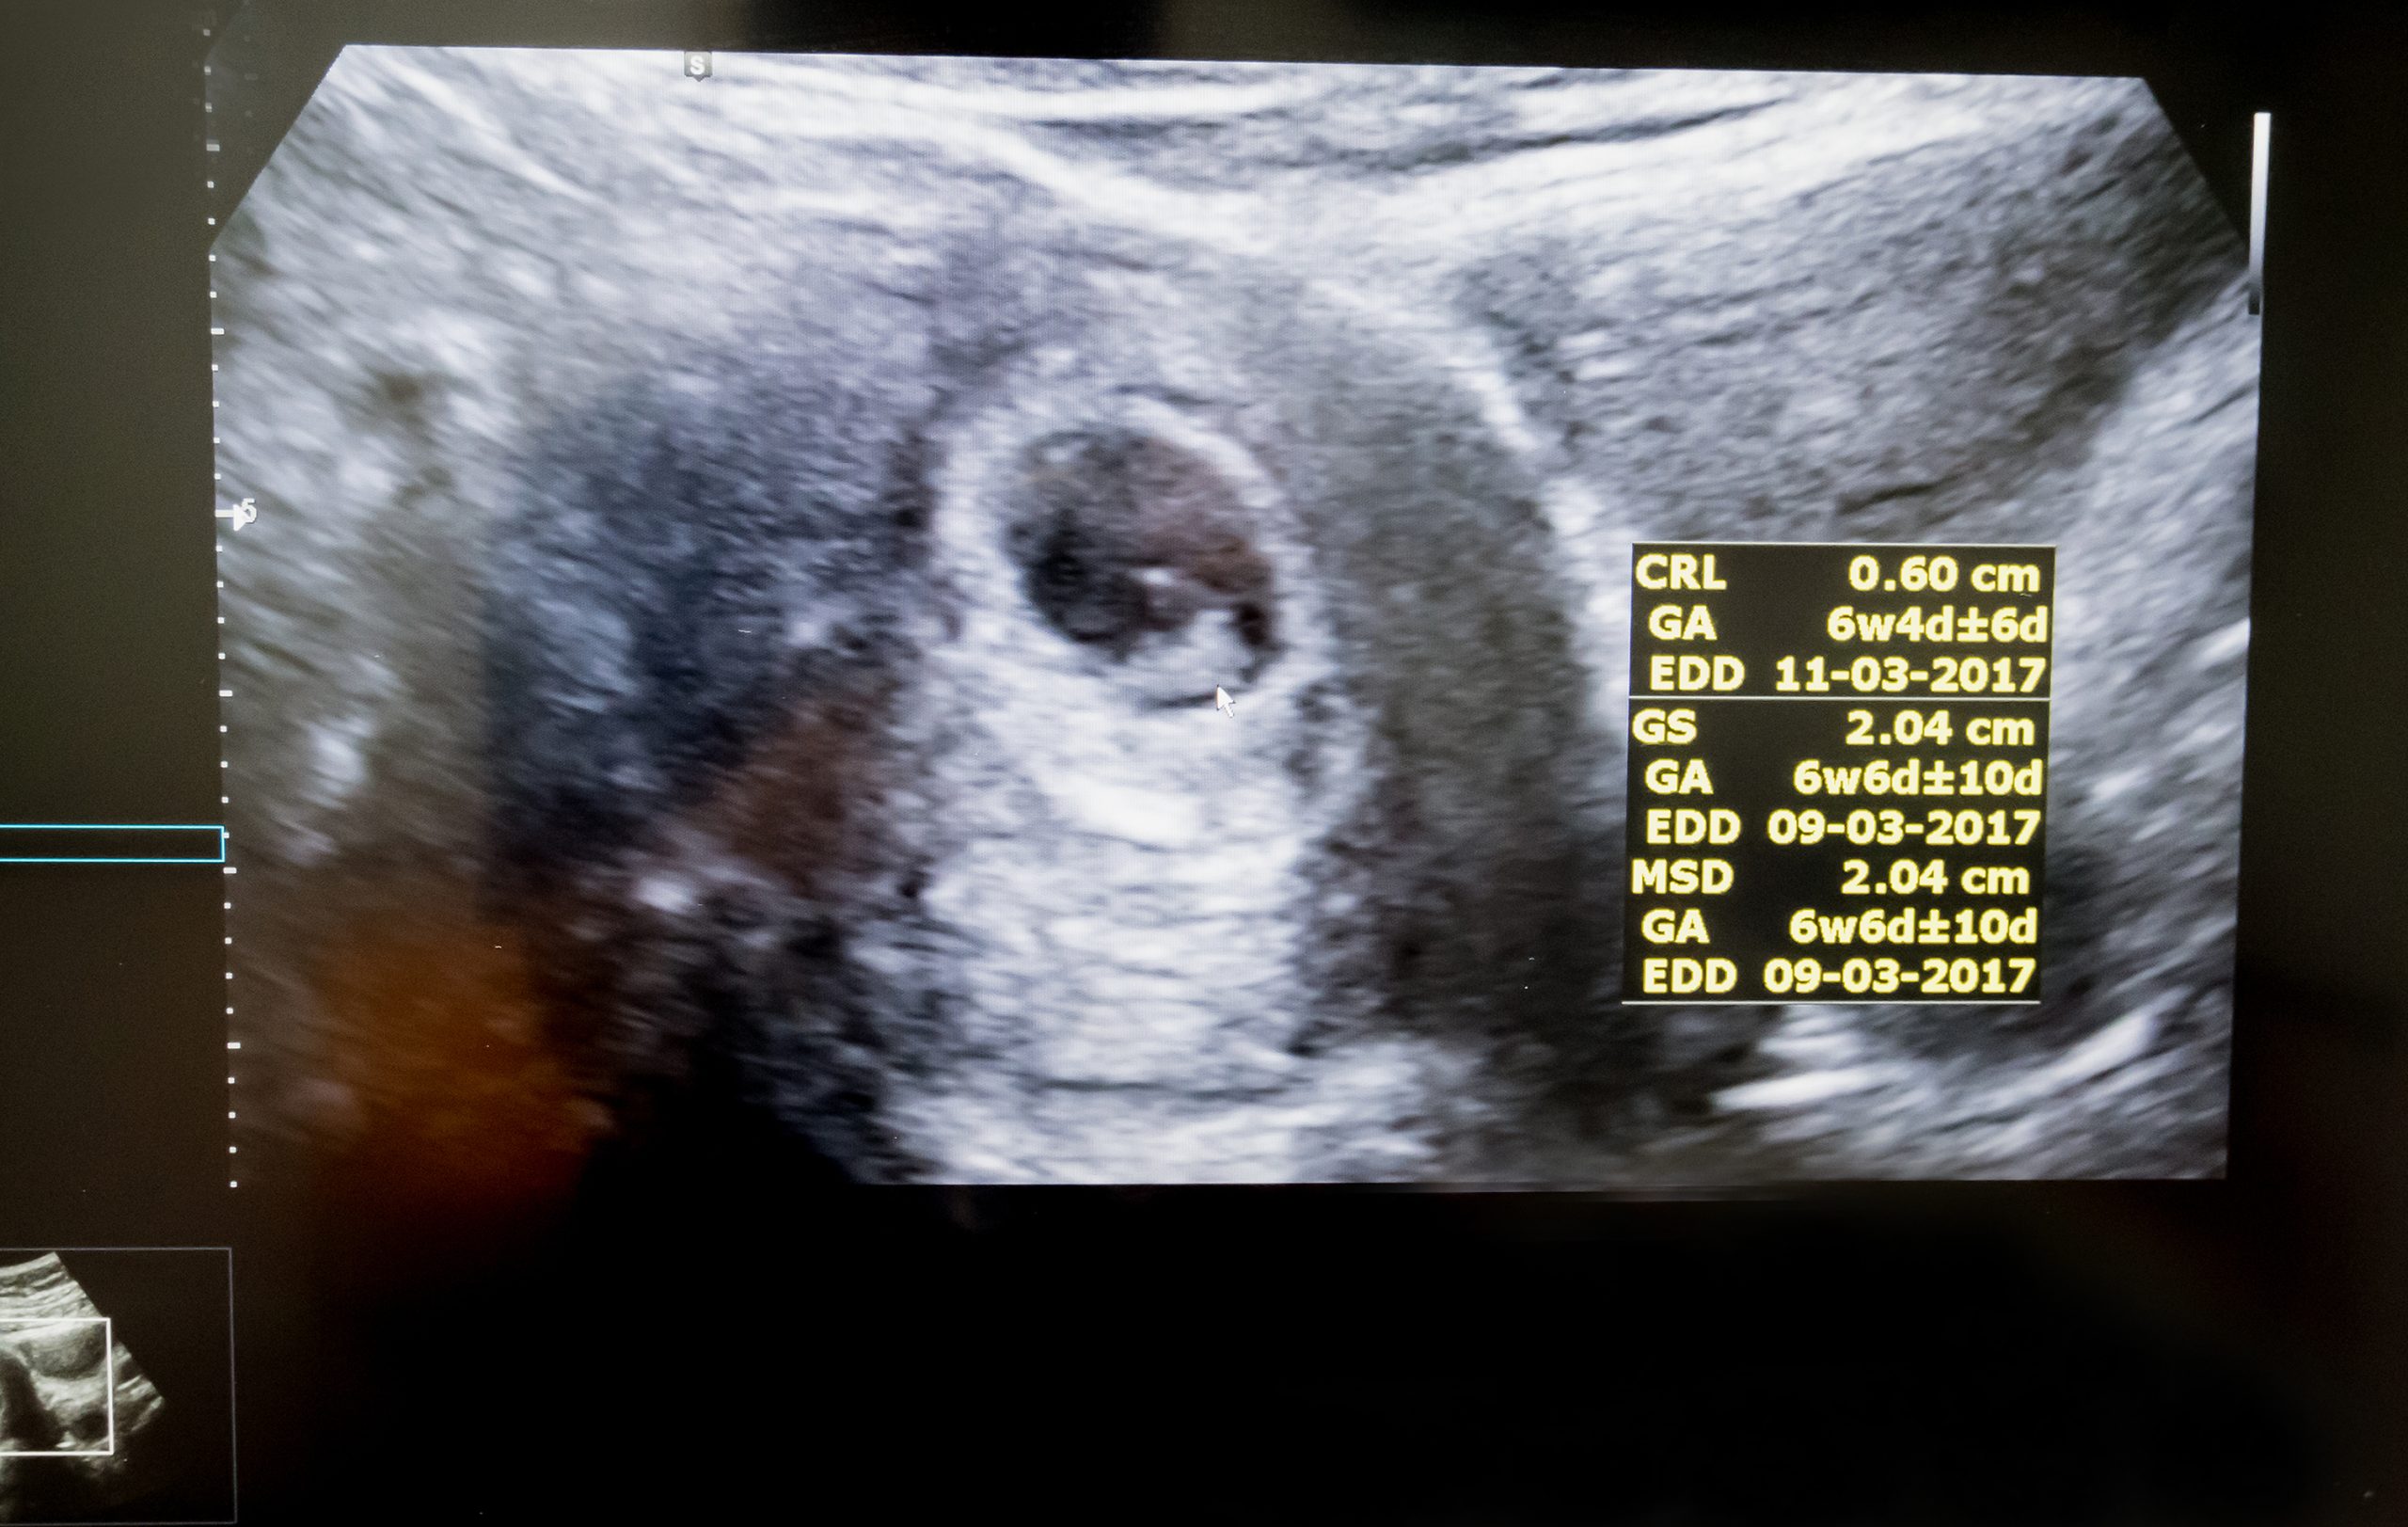

A terhesség első heteiben az ultrahangfotók még alig mutatnak többet egy apró, pulzáló pontnál, amely a fejlődő embriót jelzi. Az első trimeszter végére azonban már jól kivehetővé válik a fej és a végtagok kezdeménye, sőt, egyes esetekben a baba mozgása is megfigyelhető. Ezek a korai képek gyakran homályosak, mégis hatalmas érzelmi jelentőséggel bírnak a leendő szülők számára.